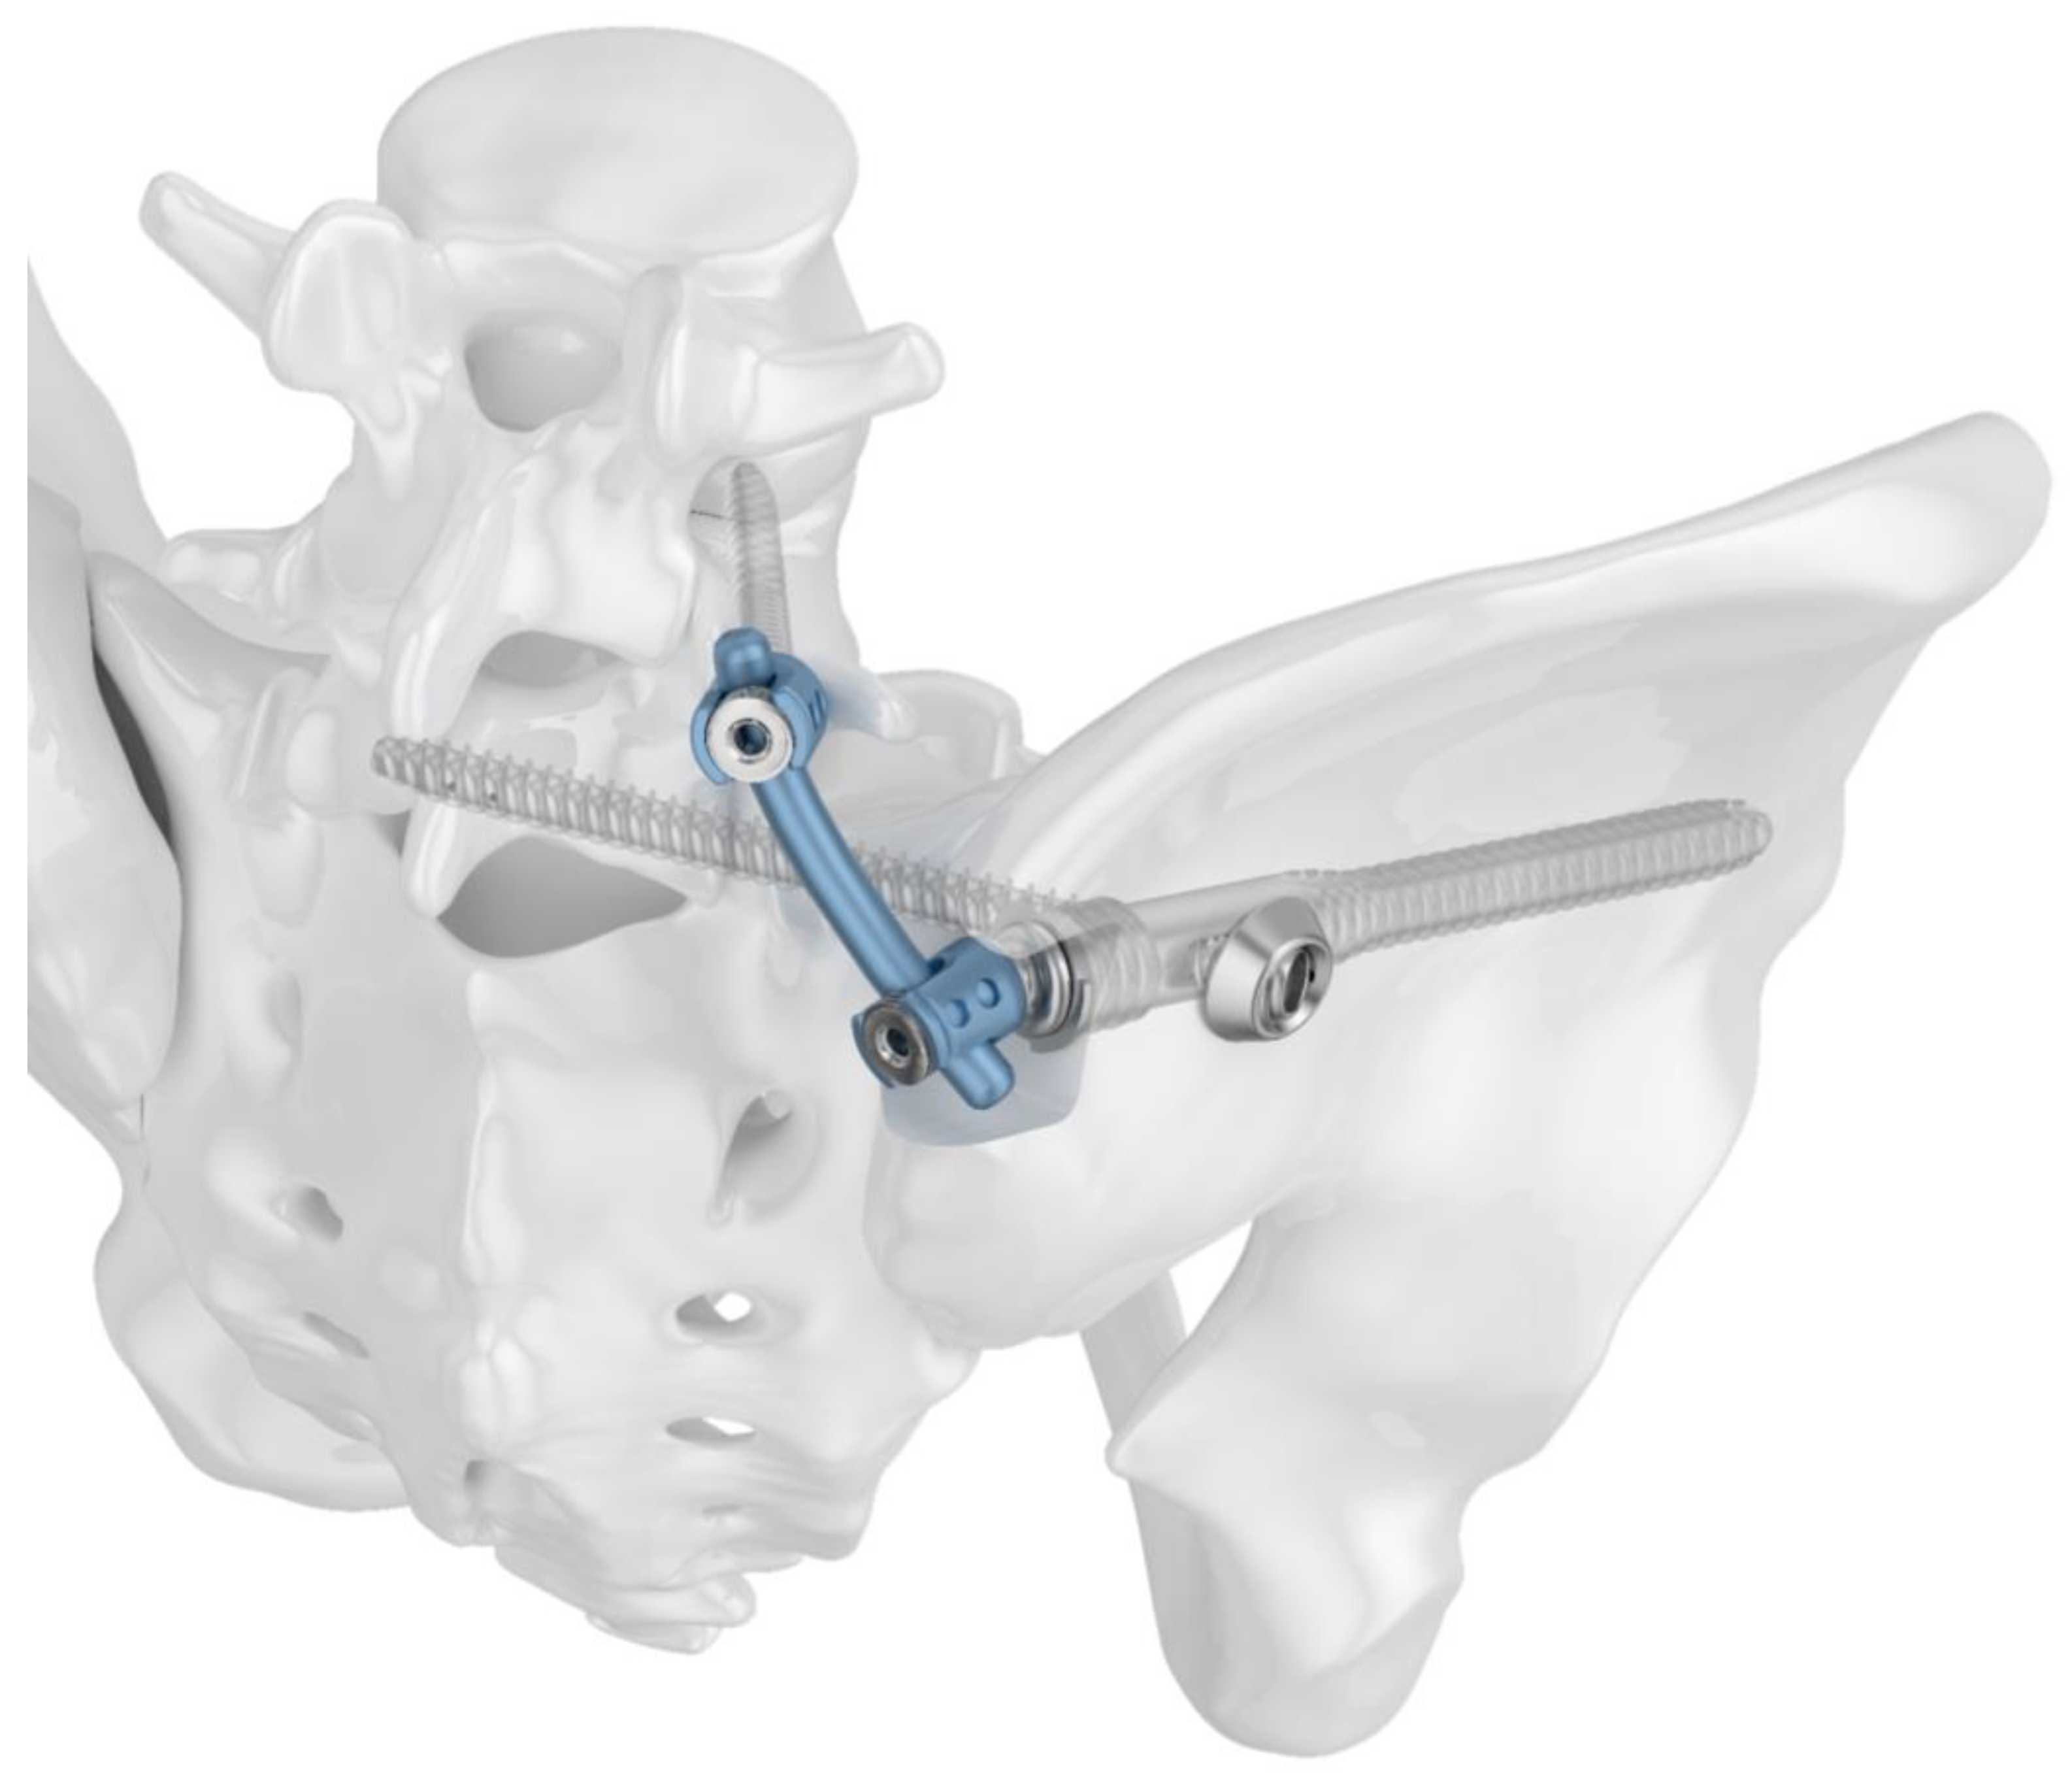

2.1. Implants

2.3. Fracture Model and Instrumentation